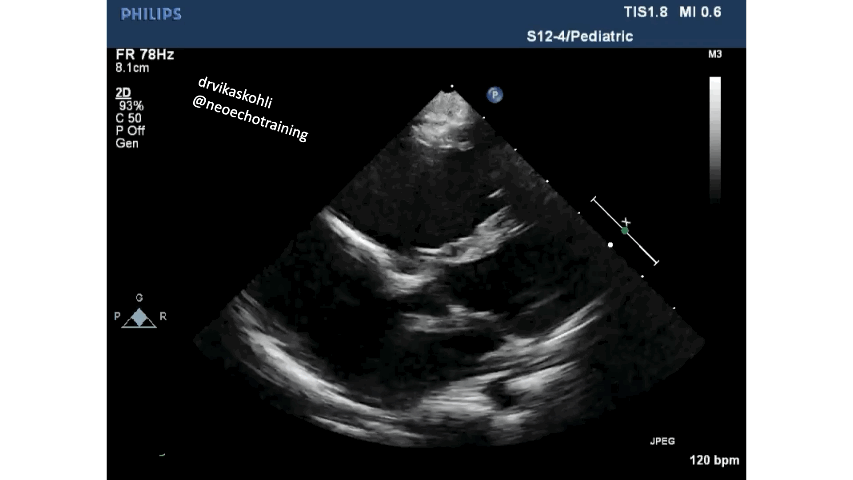

Ebstein’s anomaly is a rare condition that can present at any age. The severity of Ebstein’s anomaly directly correlates with the age of presentation, starting in fetal life to adulthood. The spectrum of this condition results in a variety of presentations from asymptomatic to severe cyanosis or life-threatening. We will go through recognition and diagnosis of this condition in apical views.

The diagnostic abnormality includes:

Displacement of Septal leaflet of tricuspid valve apically.